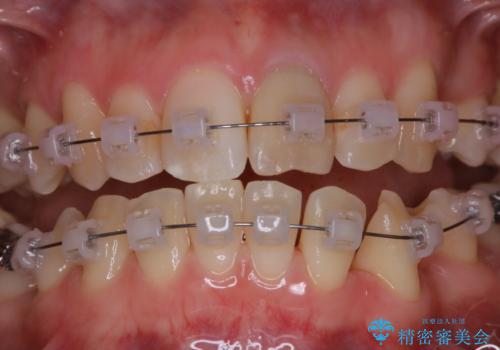

- ワイヤー矯正中に、口臭や汚れが気になり綺麗にクリーニングしたいとのことでした。染め出しをしての歯磨き指導とPMTC60分コースを行いました。

ワイヤー矯正中はブラッシングが難しくなるため、磨き残しが多くなることがあります。

ご自身でのブラッシングケアでは、歯周ポケットの中に歯ブラシの毛先が届くのはわずか2ミリ程です。軽度の歯周炎の場合でも歯周ポケットは3ミリほどあります。歯茎の中に長く汚れが溜まると、歯石や細菌などがつき、口臭の原因にもなります。

適切な道具を使って、適切なブラッシング方法を習得することで、磨き残しを減らすことができます。

また、矯正で歯の移動があると今までなかったところに隙間が出てきたり、ガタつきが解消されてきたりすることで、お口の中の環境が変わります。

矯正治療中も清潔な口腔内を保つことは、とても大切です。そのため、定期的に専門的な機械・材料を使用したProfessinnalcleaning(pmtc)を行うことがおススメです。